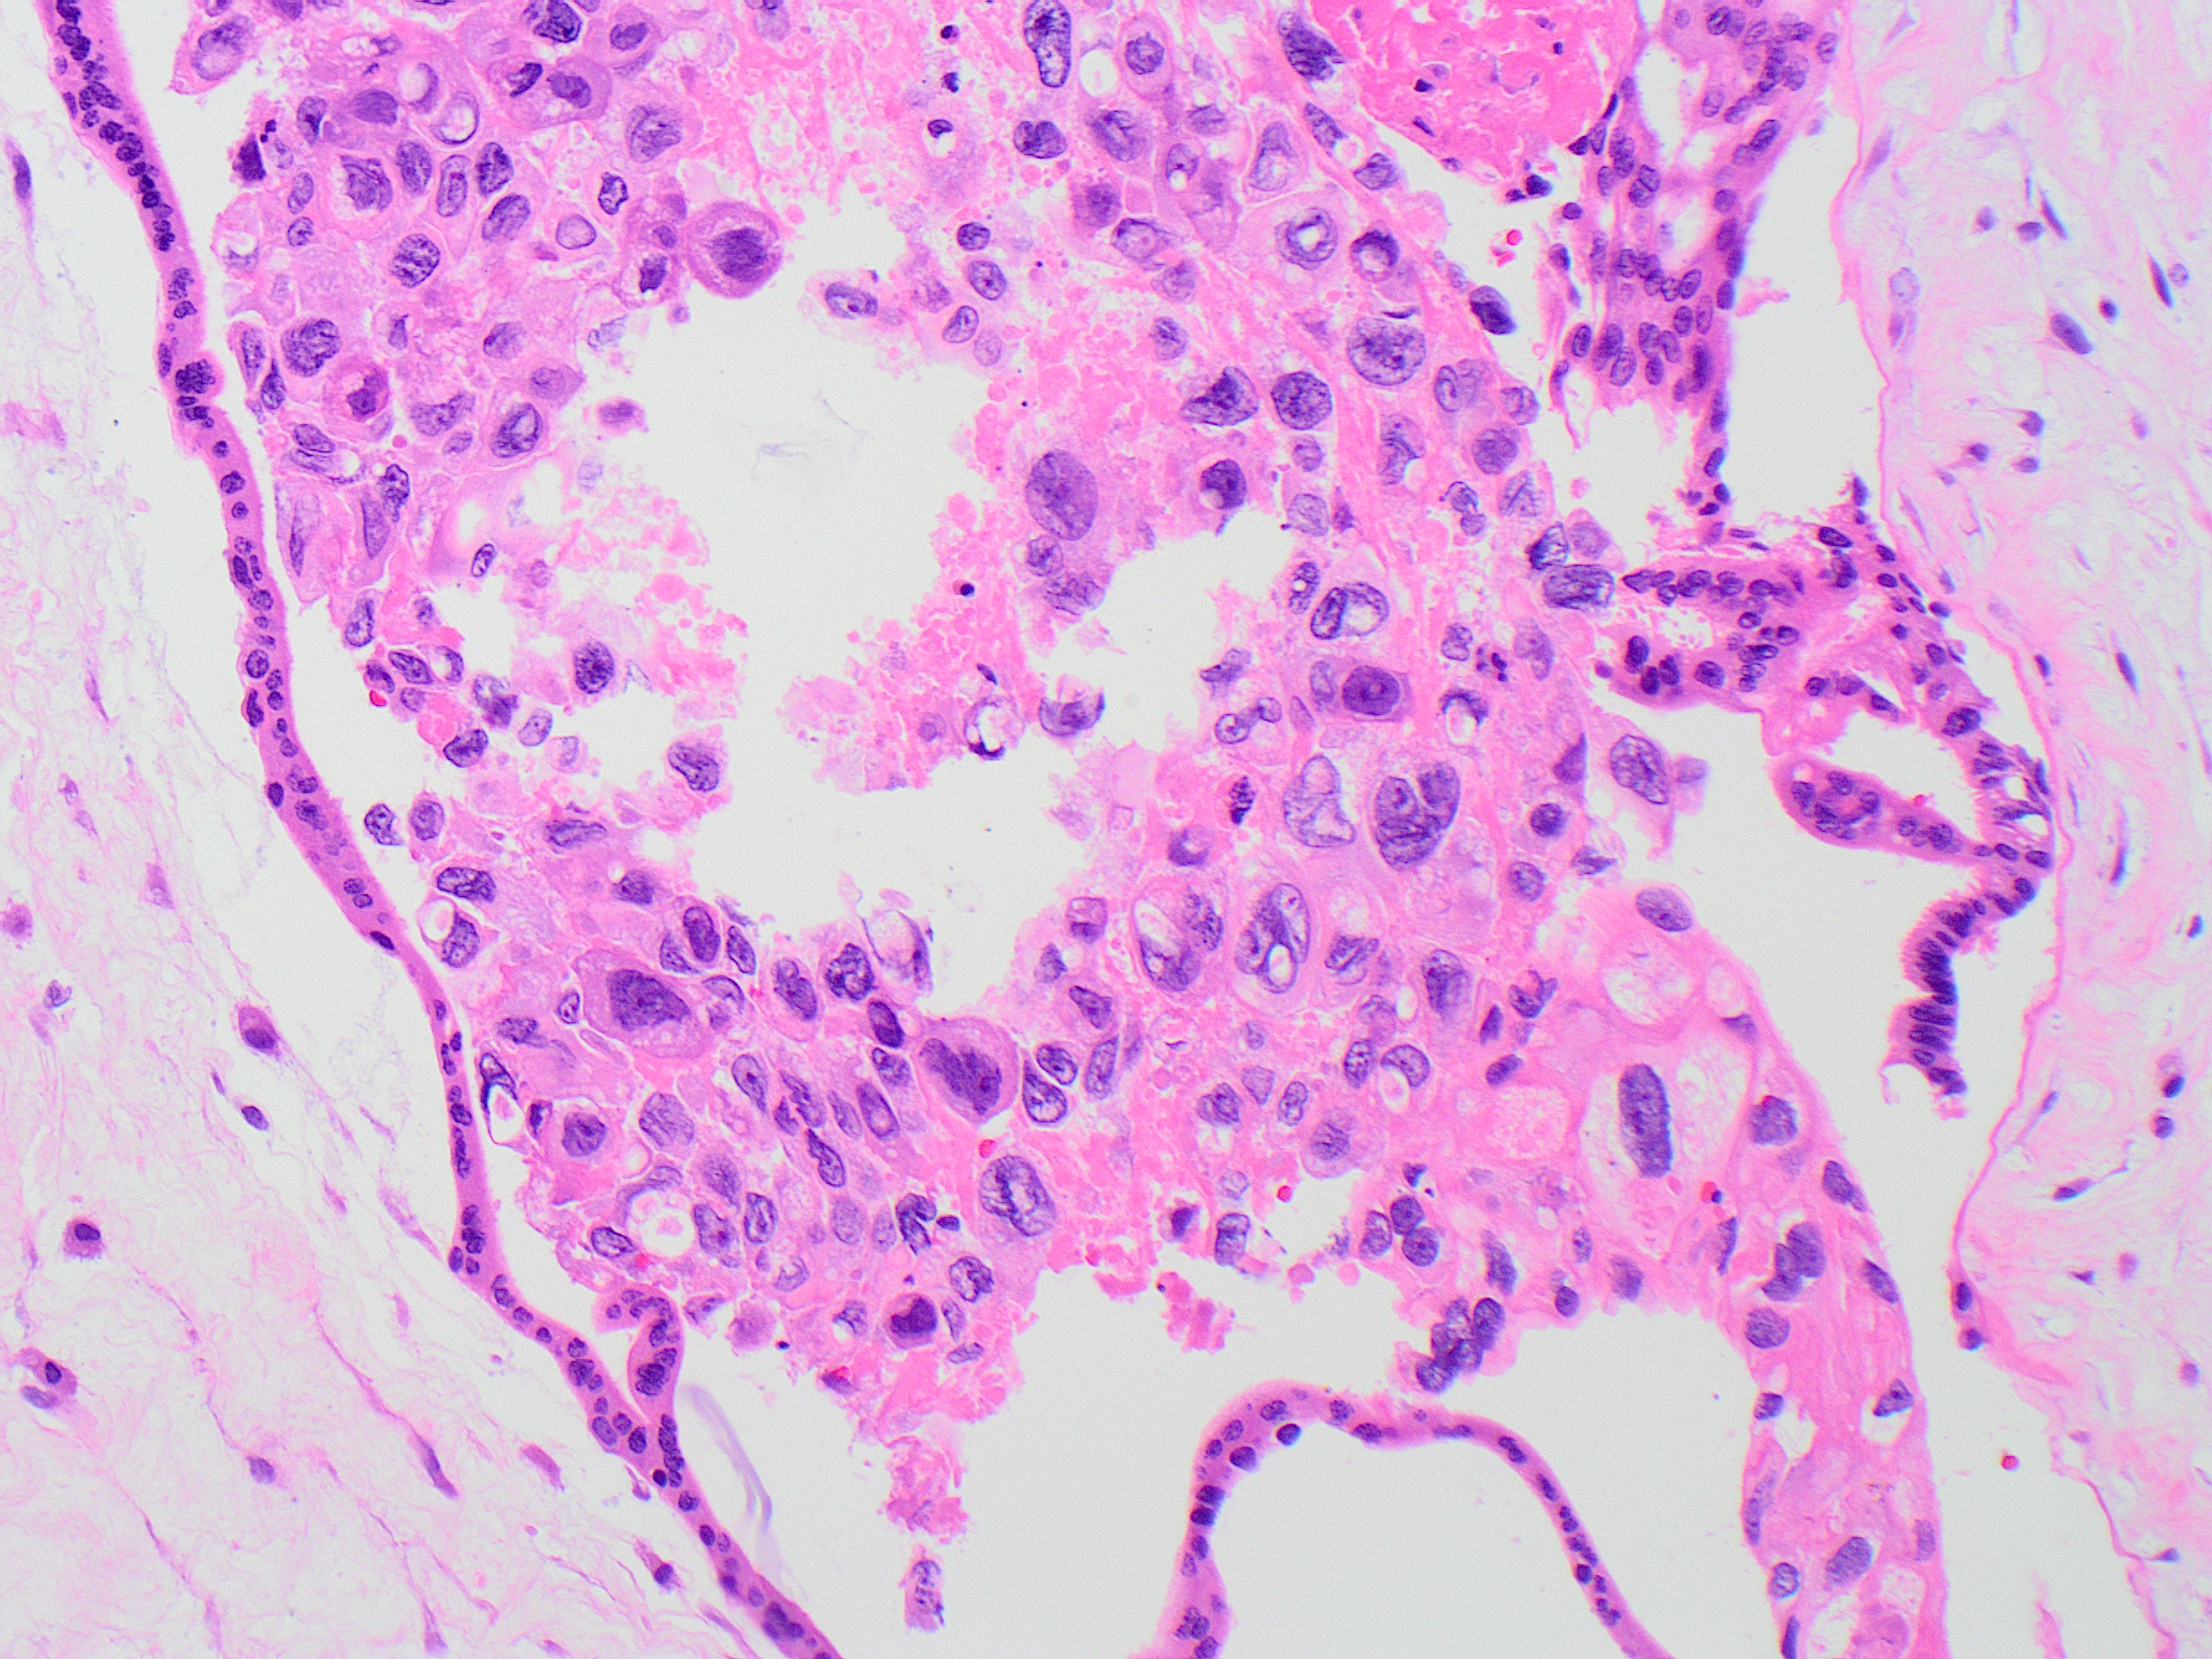

Placenta at 21 weeks. Most likely diagnosis?

Answer: B. Complete Hydatidiform Mole

The pathologic features in this case are diagnostic of complete hydatidiform mole. Complete moles are characterized by markedly hydropic villi which may grossly resemble a “bunch of grapes.” Histologically, this is evidenced by diffusely enlarged villi with central cistern formation and circumferential trophoblastic hyperplasia, which may be exuberant. Loss of p57KIP2 expression in villous stroma and cytotrophoblast is diagnostic. No fetal tissues are present in association with a complete mole.

In contrast, partial hydatidiform mole is characterized by villi of varying size and shape with scalloping of the villous borders and variably hydropic changes. Trophoblast hyperplasia tends to be less prominent than in complete moles. Because of the irregular scalloped borders, invaginations may be transected tangentially, giving rise to trophoblastic “pseudoinclusions”. Nuclei of villous stromal cells and cytotrophoblast classically retain p57 staining. Fetal tissue may be present in these specimens.